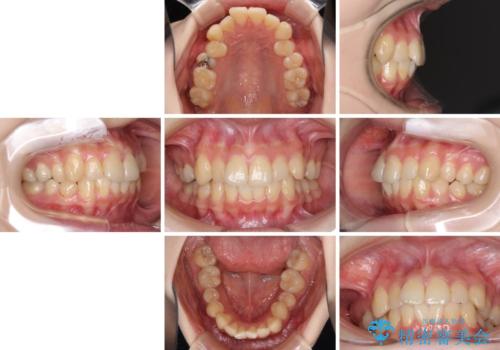

デコボコ歯列をきれいに インビザラインによる矯正治療

- 上下歯列全体のデコボコを気にして来院された患者様です。

主に下顎歯列全体の後方移動とIPR(歯と歯の間を削る)によってデコボコが解消するように設計し、インビザラインにより治療を行うこととしました。

奥歯の知覚過敏が顕著となり、その影響で奥歯の咬み合わせ改善のための顎間ゴムの装着ができず、咬合を仕上げるまでに長い期間を要することとなりました。